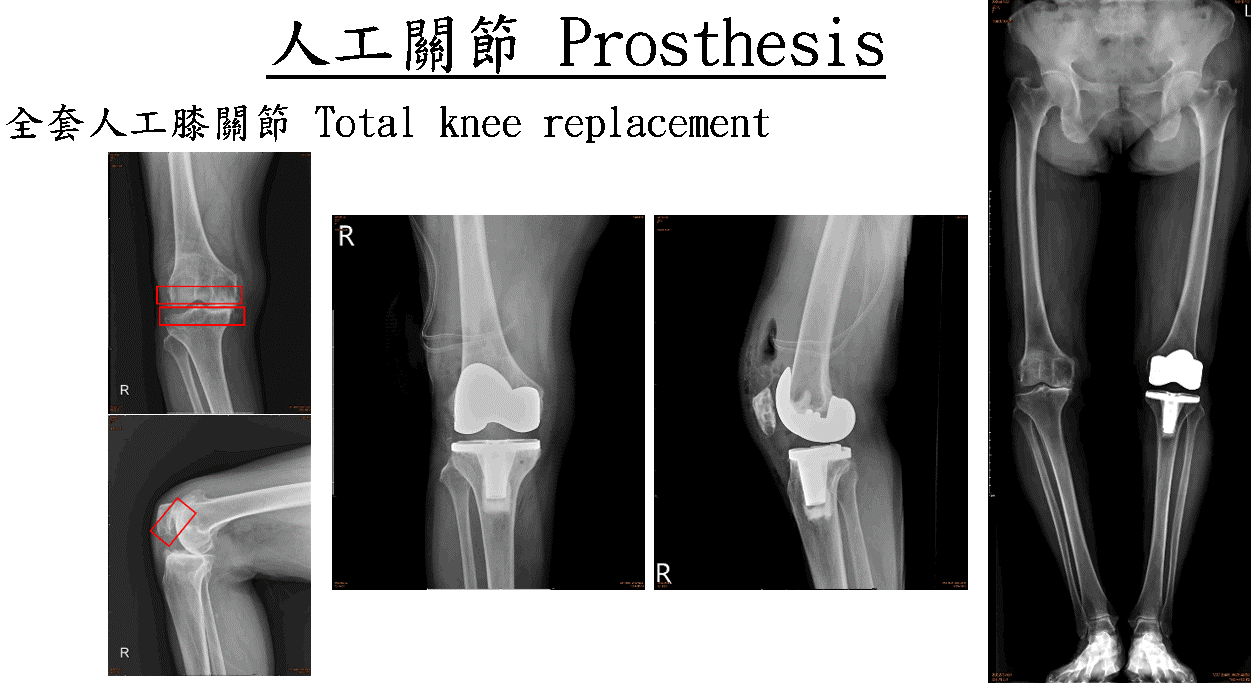

2. Artificial joint reconstruction disease-specific certification

8. Total knee artificial joint surgery

2. Artificial joint reconstruction disease certification